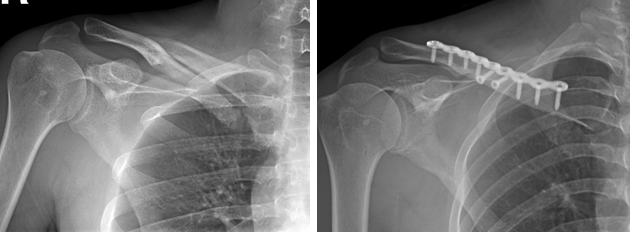

锁骨骨折

术前                            术后